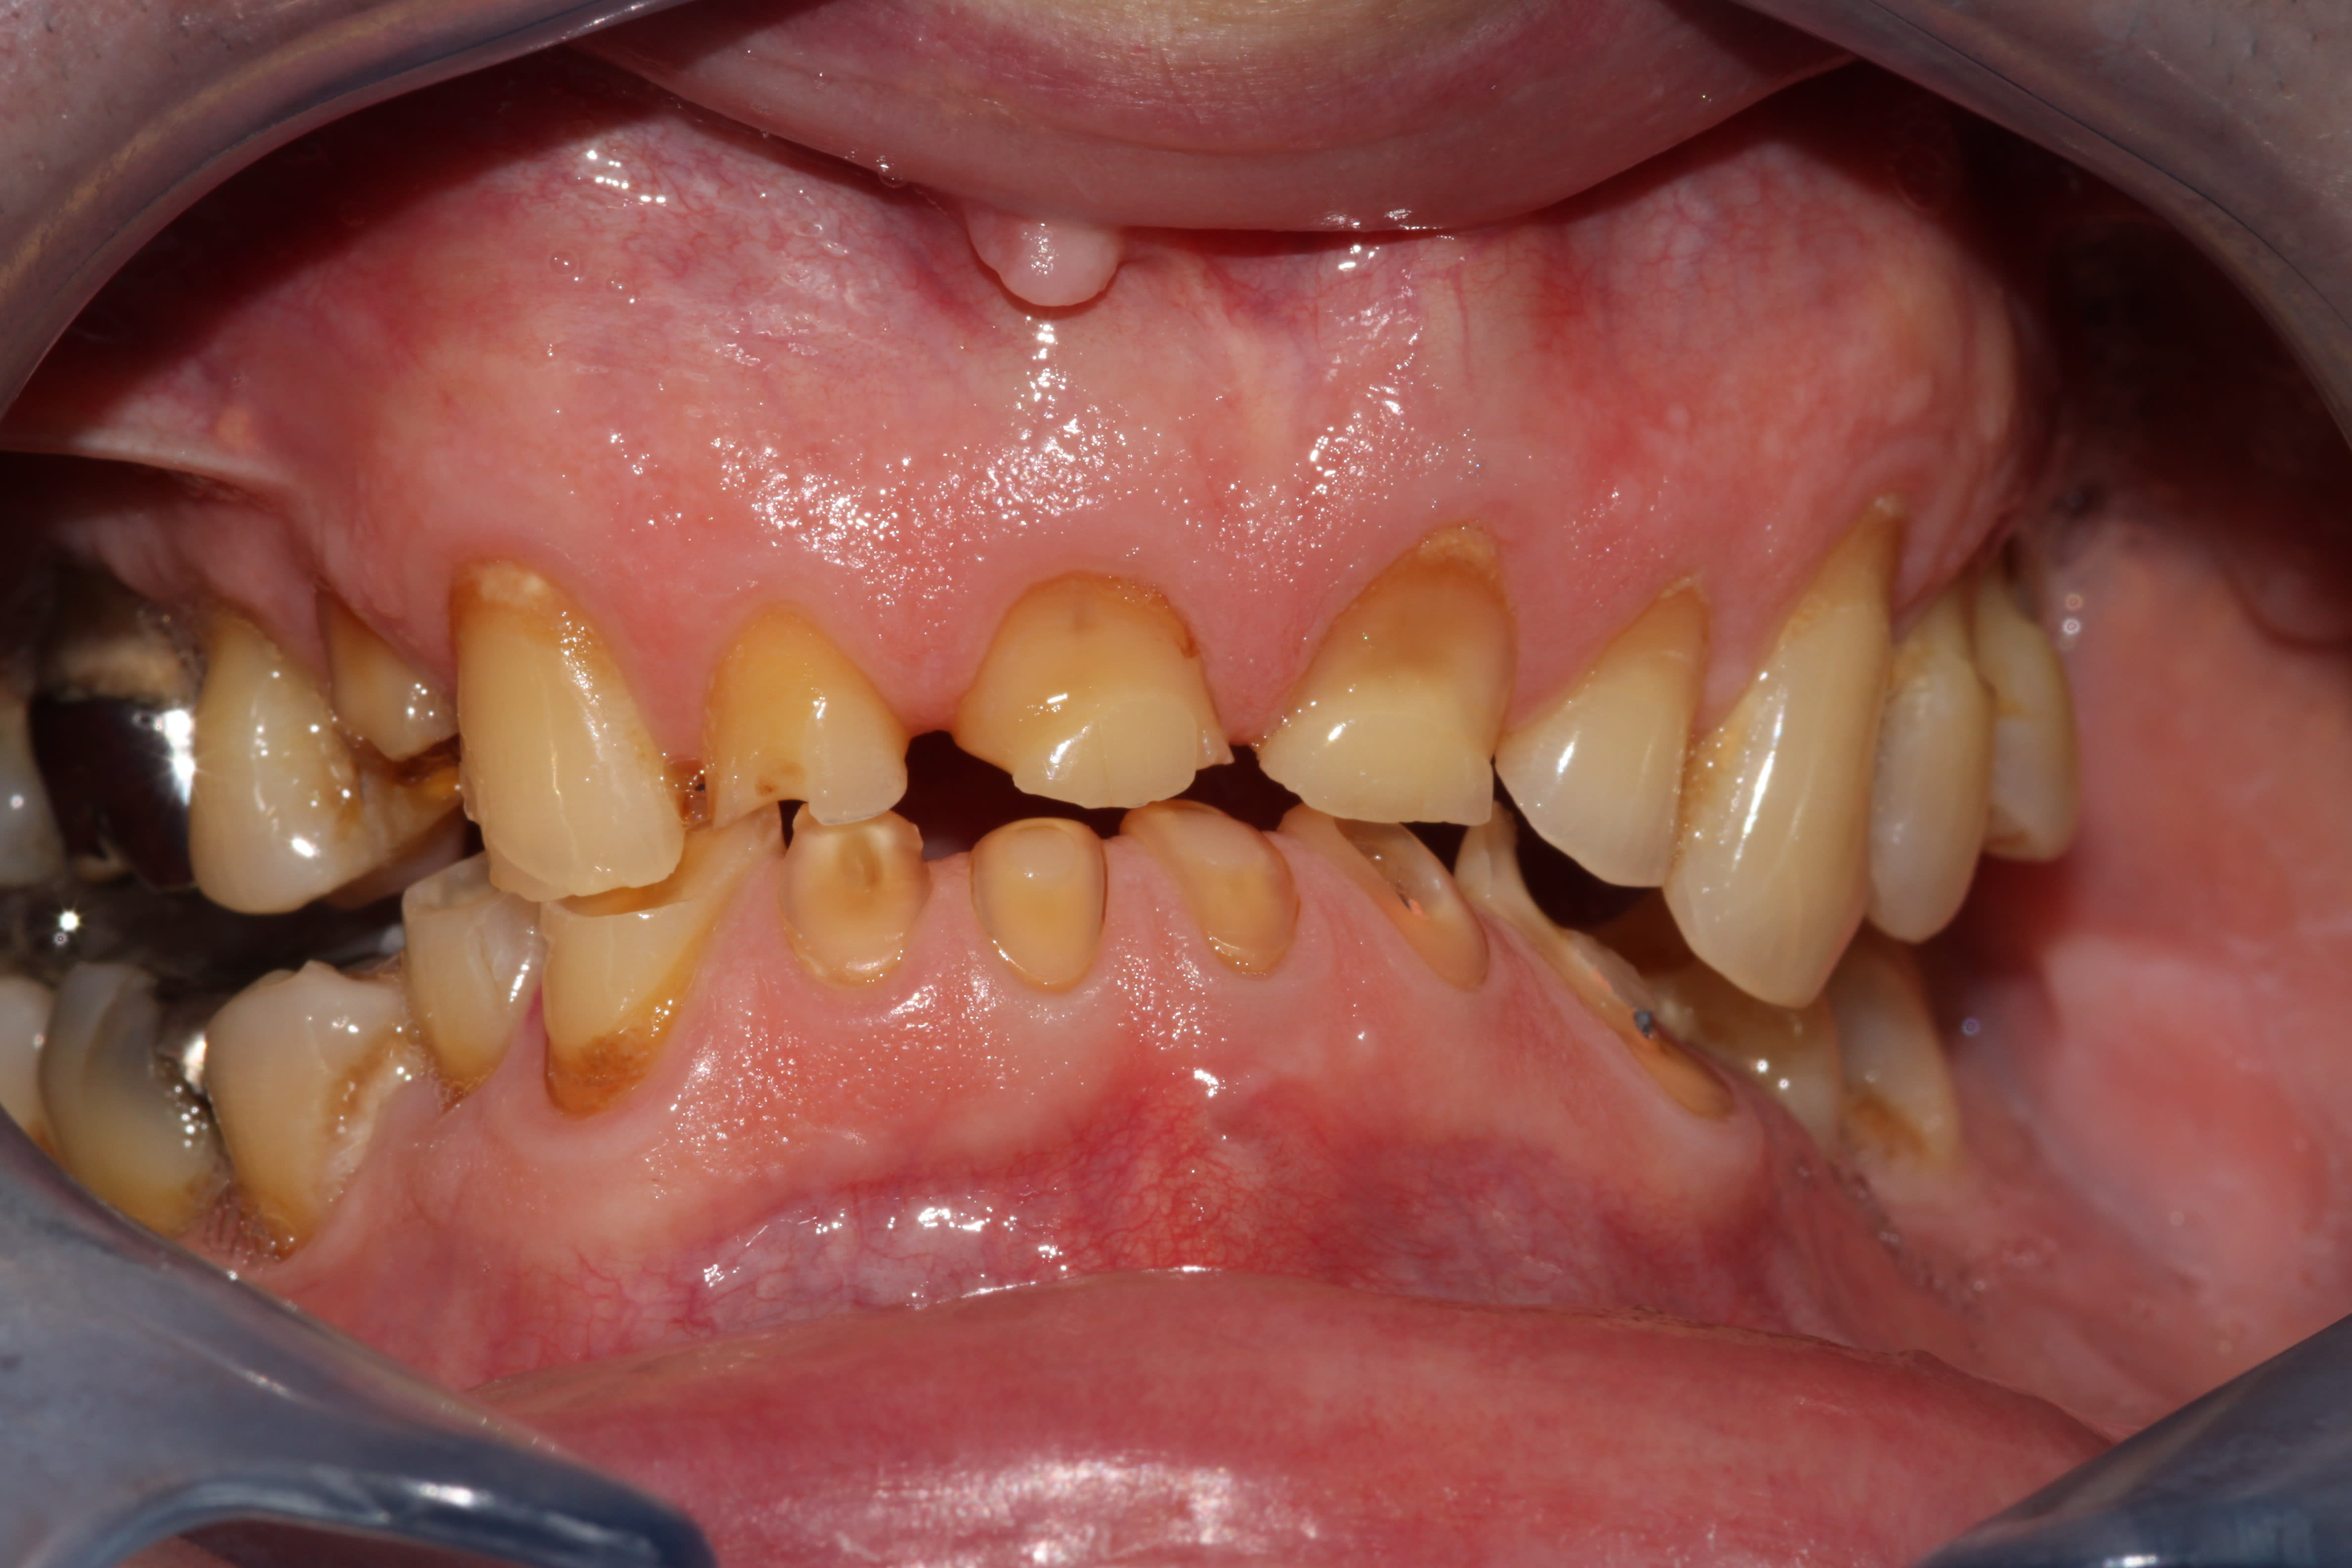

J'avais eu un boulot comme ça, probablement, le plus compliqué que j'ai jamais eu à gérer, les dents à ras la gencive genre attaque chimique interdite par la convention de Genève, et dv parfaitement conservée. Les incisives mandibulaires avaient fini à la benne pour faire de la place.

Je jette un oeil pour voir si je retrouve les photos.

Edit: a y est j'ai retrouvé. Même l'endo avait été une chierie sans nom, toutes calcifiées, toutes les mono-radiculées avaient 2 canaux distincts, j'avais perforé la 45 en tirant de travers...

Img 4061 ru6pto - Eugenol